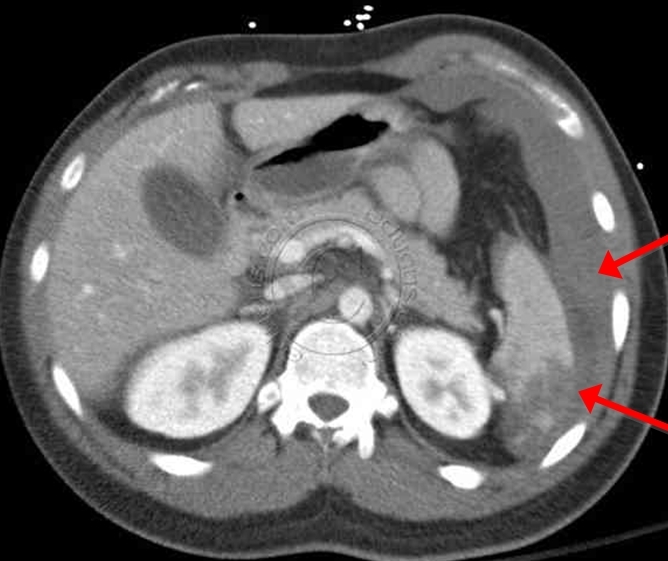

The liver and spleen are at high-risk for injury during blunt abdominal trauma.

CT scan of the abdomen gives detailed information about the pathology and source of hemorrhage (if present). It may also assist in planning of operative intervention.

Irritation of the diaphragm (e.g. due to splenic rupture) may cause referred pain to the shoulder area, typically the left shoulder. This is known as Kehr’s sign.